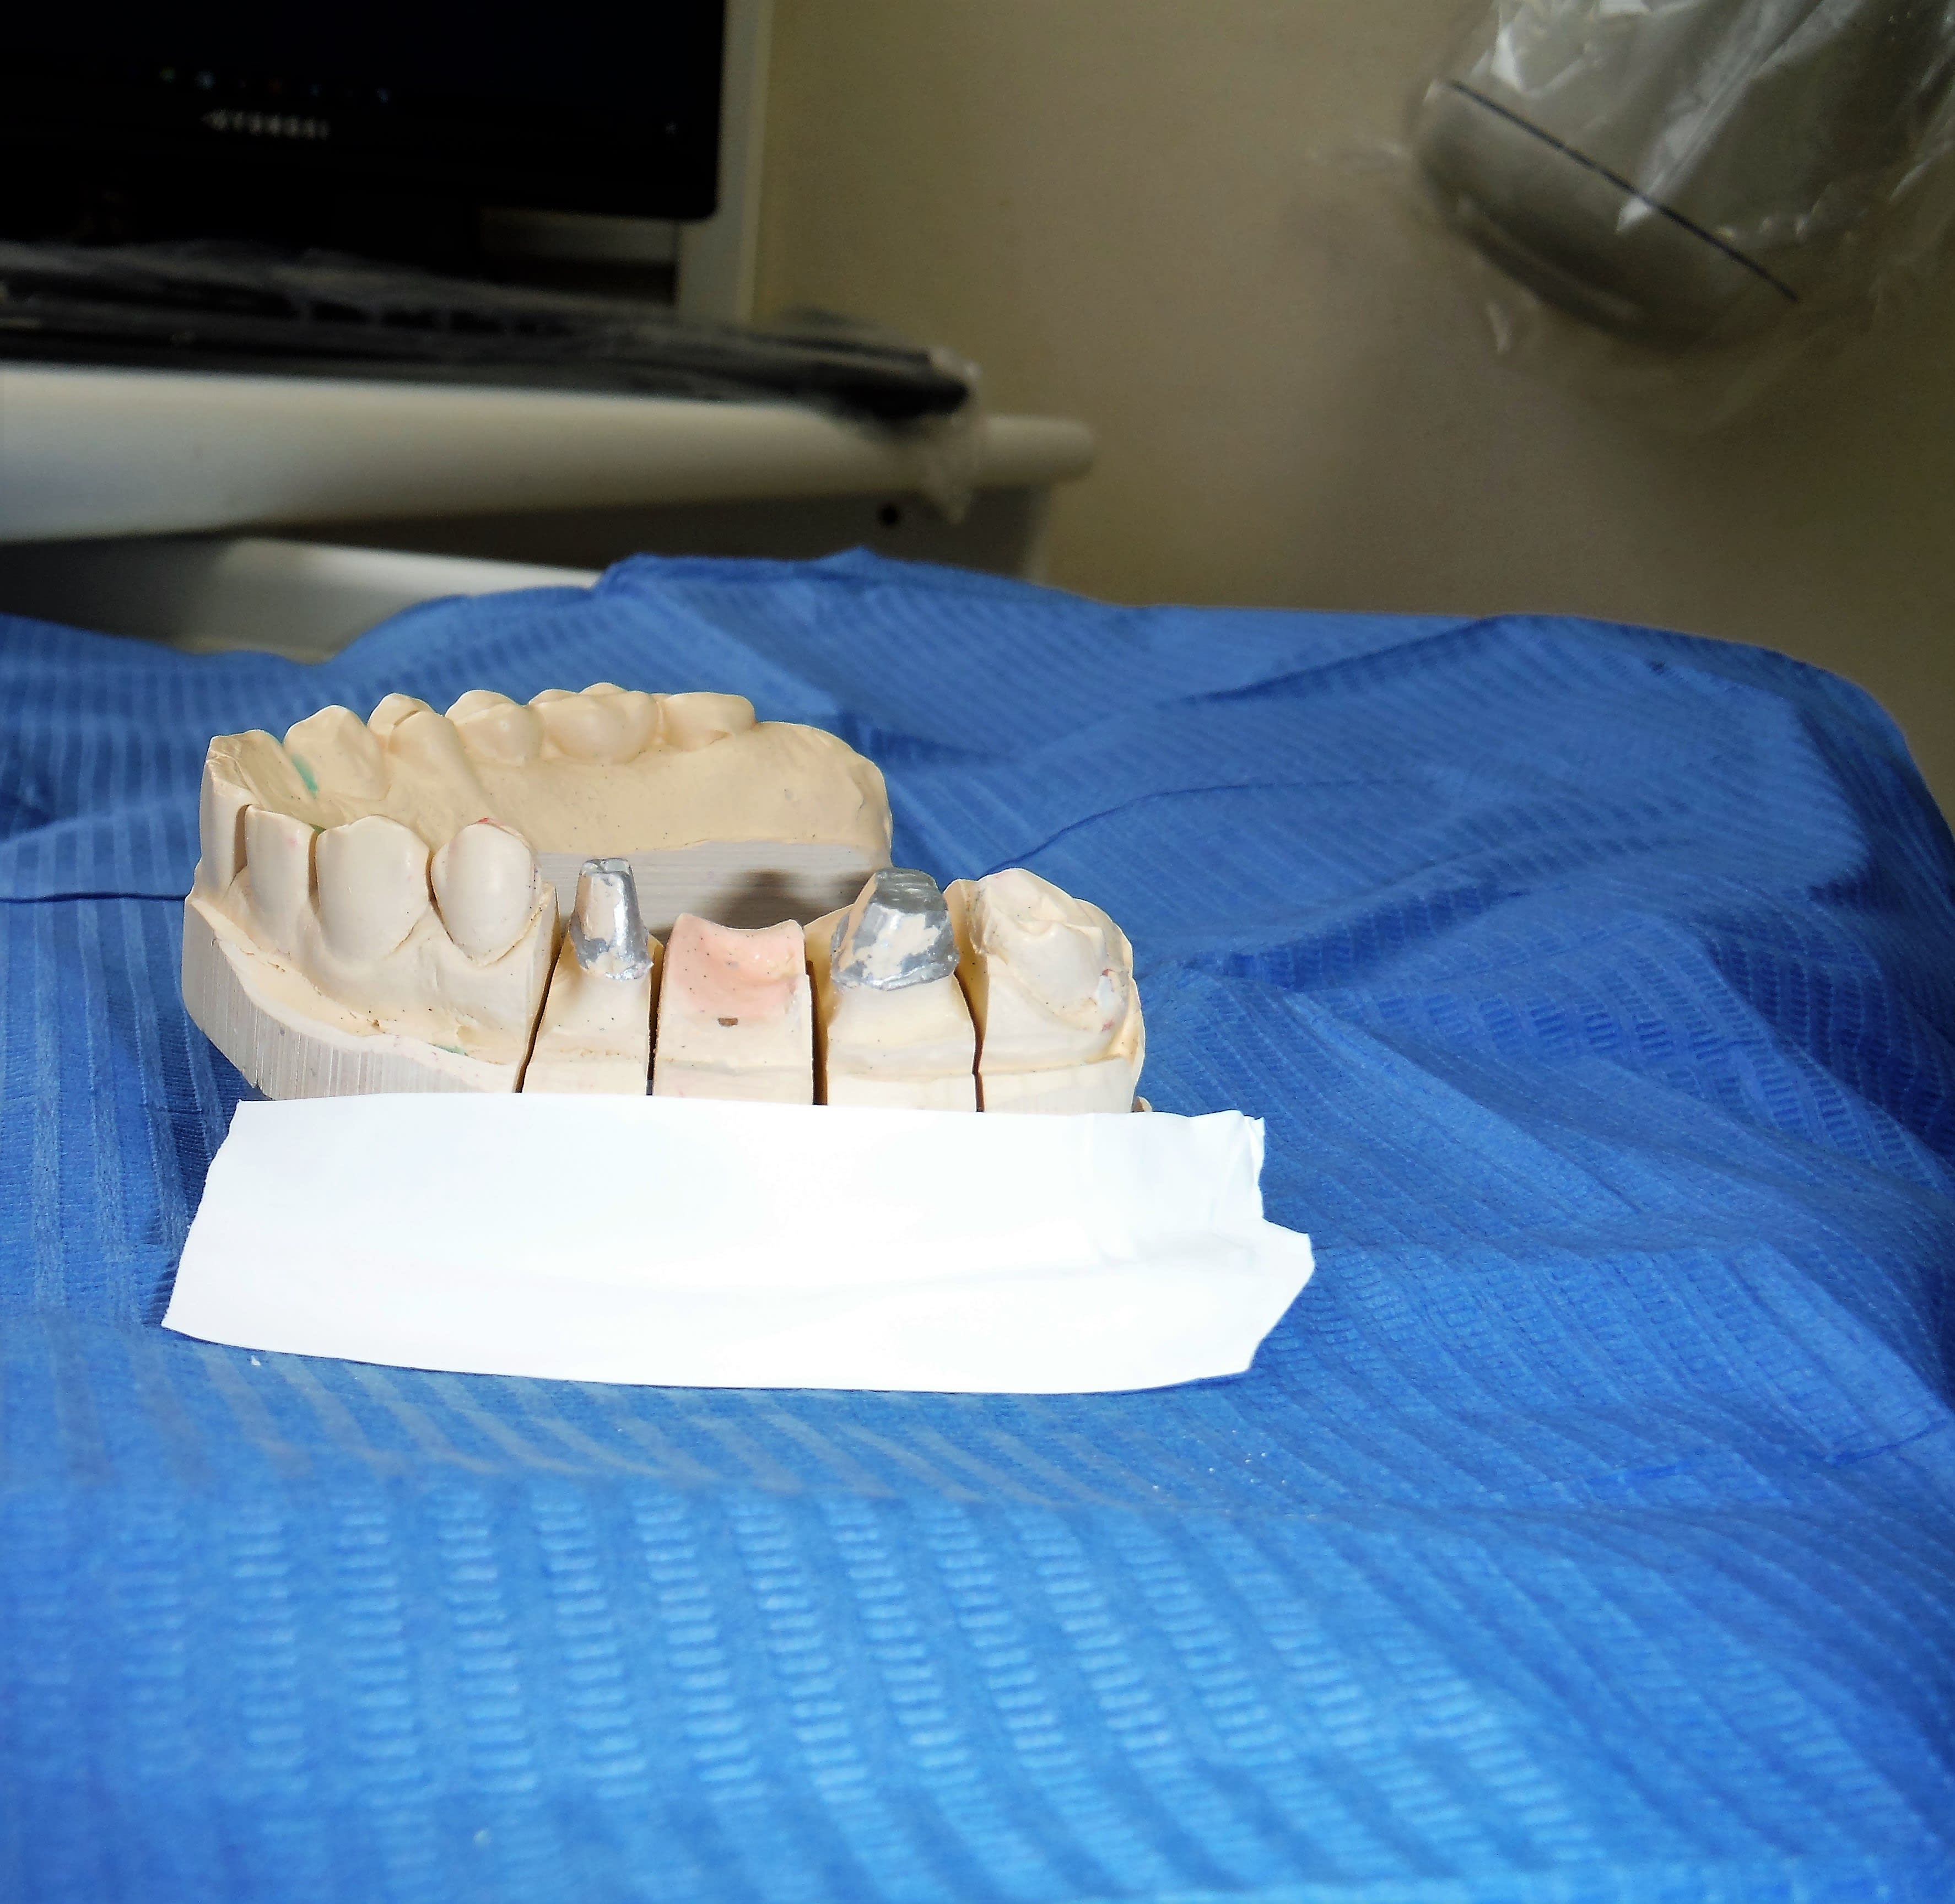

23/02/2017 à 14h25

Je suis en train de tester un autre labo spécialisé en "chinoiserie" comme le dit Enlaye.

Là je leur ai demandé de me faire une prémolaire ayant une forme de canine . (Absence de canine)

Et là c'est 13-14-15 bridge CCM ... toujours le nouveau labo spécialisé en chinoiserie que je suis en train de tester